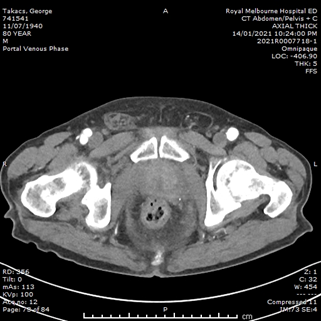

He had normal inflammatory markers, Hb 133g/L and Creatinine 104umol/L. A Computed Tomography (CT) scan of the abdomen and pelvis was performed, with the differentials considered being incarcerated inguinal hernia, diverticulitis or malignancy. However, the CT showed a 75mm, contained ruptured right internal iliac artery (IIA) aneurysm, with no active contrast extravasation (Figure 1). There was perianeurysmal haemorrhage in the right iliac fossa which extended into a small fat-containing inguinal hernia (Figure 2). There was also bladder distension and moderate-to-severe right hydroureteronephrosis secondary to the large aneurysm.

Figure 2 CT images of the abdomen and pelvis. (A) Coronal image showing perianeurysmal haemorrhage in the right iliac fossa extending into an inguinal hernia. (B) Axial image showing the right inguinal hernia containing blood, as compared to left inguinal hernia containing fat only.